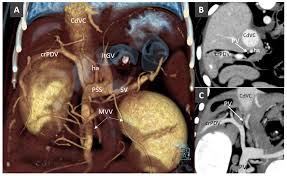

Liver shunt is either present at birth (a congenital portosystemic shunt) or it develops later in life (an intrahepatic liver shunt: A liver shunt called the ductus venosus is actually a natural development while a puppy is growing inside the mother's uterus. A medical treatment is then recommended. There are both medical and surgical treatment options for liver shunts with varying degrees of success. Most affected puppies start showing signs within weeks of. Liver shunts are developed before birth and cannot be prevented in your cat.1 x research source to determine if your cat has liver shunts, start by identifying the physical and behavioral symptoms of this condition. Instead, all detoxification comes from the mother's liver for. Blood is unable to be properly filtered by the puppy liver. 0.3 extra diagnostic tests detect a liver shunt in puppies. Treatment of choice for congenital shunt is partial or complete surgical ligation of the anomalous vessel; Without treatment, toxins circulating throughout their bodies eventually cause organ failure and the dogs liver shunt primarily affects small breeds; Clinical trials help our veterinarians discover new ways to diagnose, prevent, and treat conditions that affect your pet. Interestingly, during gestation, puppies' livers aren't functional.

However, shunts have been diagnosed in adults. A liver shunt called the ductus venosus is actually a natural development while a puppy is growing inside the mother's uterus. They specialize in liver shunt surgery. For treatment, the veterinarian may do a surgical closure. Many puppies with liver shunt become blind. Medical treatment will buy time, whereas surgical treatment can provide a cure. Congenital portosystemic shunts (aka liver shunts) are relatively common birth defects in pets where the blood vessels in the abdomen develop abnormally and instead of funneling blood from the intestines through the liver, the blood is able to bypass the liver and enters the systemic circulation. They eat very little dog food.